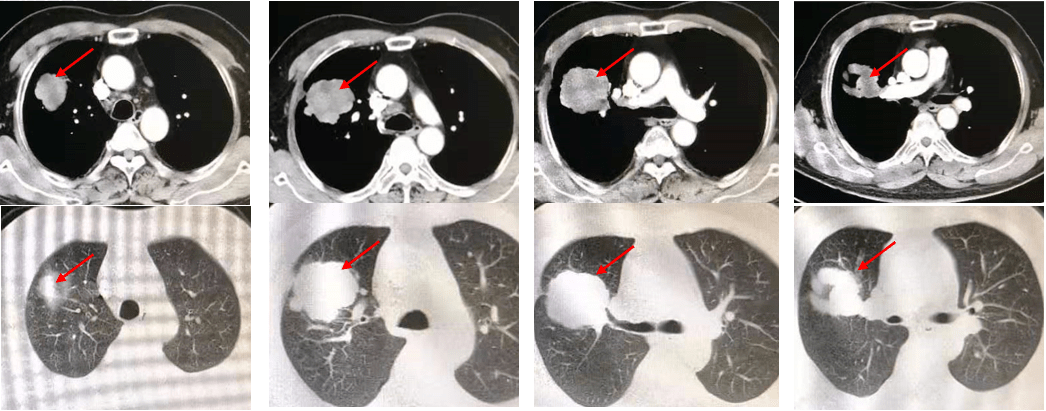

肿瘤的微创热消融治疗_病灶_右肺_患者

增强ct示:肺部感染吸收,左下肺占位无明显变化,考虑恶性肿瘤不除外

胸部增强ct(2020年1月31日):右肺上叶前段软组织肿物(5.

入院后在常规ct检查中发现患者存在肺部占位的情况,疑似患有肺部肿瘤

无明显变化考虑机化性肺炎可能性大但不能除外肿瘤性病变pet/ct检查